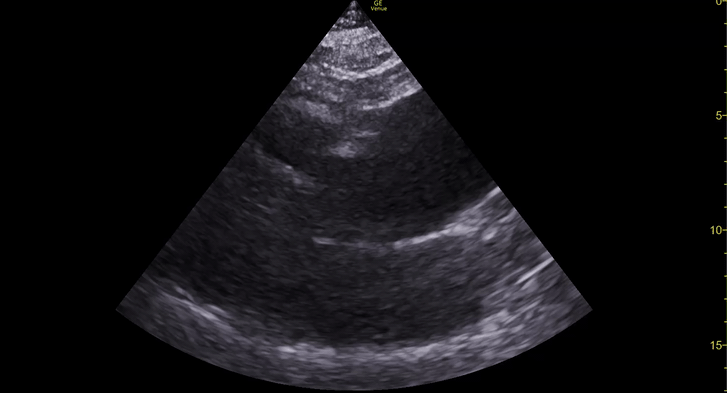

The IVC diameter changes depending on intravascular volume status, and normally, the IVC collapses during spontaneous inspiration. Therefore, the IVC diameter represents a non-invasive method for estimating central venous pressure (CVP). The evidence suggests that in spontaneously breathing patients, there is a good correlation between the sonographic estimation of CVP and values measured with invasive methods (2). IVC filling and CVP, however, allow only a rough correlation with volume status, and the sonographic estimation of preload should at least include the assessment of the LV and the Lung. Thus, it is better to think of IVC filling as an indicator of fluid tolerance, instead of a determinant of fluid responsiveness (6).

IVC exploration is best from the subxiphoid approach with longitudinal and transverse images. The IVC should be assessed in terms of overall size and collapsibility. The diameter is typically measured at its largest (end of expiration) at 1-2 cm distal to where the hepatic veins join the vena cava. An IVC diameter of ≥ 2 cm, especially with minimal or no collapsibility, is considered plethoric and correlates with increased RA pressure. An IVC of < 1 cm, particularly with complete collapse, is considered flat and indicates low preload and potential fluid responsiveness. An IVC diameter between 1 and 2 cm is typically normal.

PITFALLS

In a long-axis view, beware of not sliding off the centre of the vessel, as this will underestimate the size of the IVC and overestimate its collapse. Obtaining long and short axis views may help avoid this pitfall. Another mistake is confusing the descending aorta for the IVC, particularly when scanning in long-axis. Although the IVC may appear to pulsate, the aorta has a thicker wall, and its position is to the patient’s left. Following the IVC upwards will reveal the hepatic veins junction and the entrance to the RA, while the aorta will travel behind the heart. The IVC moves both anterolaterally and craniocaudally with inspiration, and this should be considered during visualization or measuring. For this very reason, measuring in M-mode is not recommended as it would not be accurate.

SHOCK

In a shocked patient, a flat or highly collapsible IVC correlates well with low preload estates (hypovolaemia, haemorrhage, sepsis). Yet by itself, a small IVC is not enough to define low preload and could also represent a normal finding.

Conversely, a distended, not collapsing IVC suggests distal obstruction in a shocked patient. Potential causes include LV failure, massive PE, tension pneumothorax and cardiac tamponade. Nonetheless, there are other causes of elevated cava / RA pressure, such as chronic pulmonary hypertension.